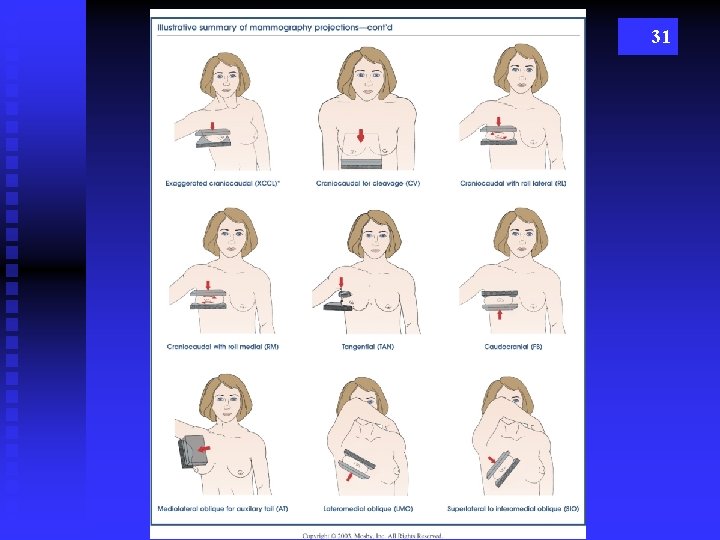

31